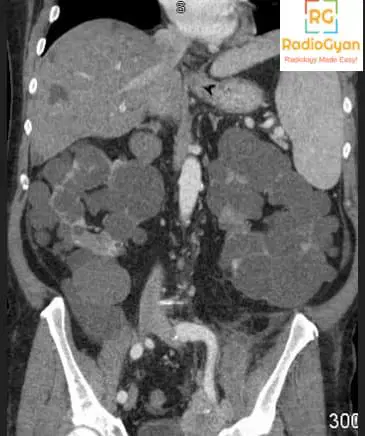

Autosomal Dominant Polycystic Kidney (ADPKD)

The diagnosis is pretty straightforward in this case for most of the radiologists and radiology residents. The kidneys are symmetrically enlarged with multiple cysts with a few cysts in the visualized liver as well. The radiology features are consistent with Autosomal Dominant Polycystic Kidney (ADPKD). But is diagnosis enough in this case? Is this the reason why the referring clinician has sent the patient? Read on to find out.

- Cysts in other organs like liver, ovaries, spleen. seminal vesicles, prostate, and pancreas.